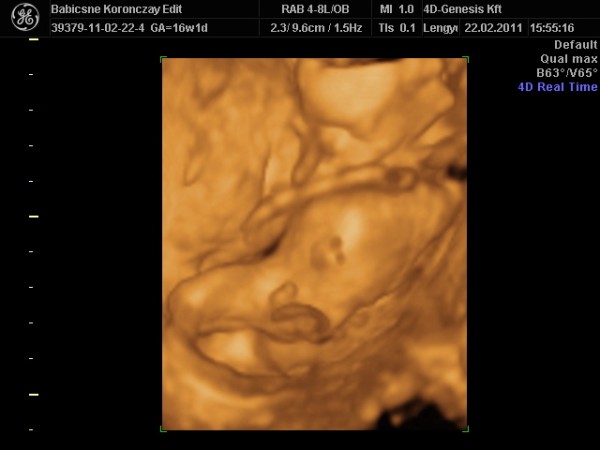

Végül is ma megyek a 4D Genesisbe!!!! Felhívtam őket és kaptam időpontot..annyira izgultam hogy azt mondtam: "tudja én vagyok a down-kóros" Nem győztem kijavítani magam, hogy nem úgy értettem!!!

17 cm-es egészséges KISFIÚ!!!!!!!!!!!!!!!!!!!!!!!!!!!

Alighogy bekapcsolta az uh-t és megláttuk a babát, rögtön mindneki egyszerre felkiáltott: KUKIIIIIIIIII...végig mutogatta magát..szóval lesz egy fiam :-) Hihetetlen!!!

a 4D Genesis egy csoda...romantikus félhomály, gyönyörű lassú zenék szólnak a háttérben és olyan alaposan minden apró részletet megvizsgál, hogy nem találok szavakat..a szív 4 része, az agyacskája részei, a tüdeje stb-mindent megnézett, mindent megvizsgált és mondta egy csomó apróbb jel is utalhat Down-kórra (pl. rövid nyak, rövidebb combcsontok és hosszabb karcsontok stb.stb.)...szóval nagyon rendes a nő, nem is találkoztam ilyen szakemberrel, tényleg imádja a munkáját, a babákat és tényleg úgy beszél, hogy az az érzésem, az én magzatom a legeslegszebb....kerek a feje, mint nekem, hatalmas az orra és vékony a szája, mint nekem..de összeségében apa vonásait látom ( a lányomnál pedig egyértelműen rám hasonlított az uh-on is már)

1 héttel nagyobb, át is javítom a szülés dátumát, az uh-os is átírta...szóval augusztus 1 lett az időpont, de én tuti hamarabb fogom őt is megszülni (Boncsikám is 2 héttel hamarabb érkezett) nagy gyerek már most...mellső falon és nagyon mélyen tapad a méhlepény, kérdezte is hogy nem vérzek??? De nem szerencsére...és hogy 17 cm-es..hát hatalmas..ha belegondolok, a kislányom 51 cm volt mikor megszületett :-)

És képzeljétek a kislányom kb. a vizsgálat 40. perce körül unta meg az egészet, de szerencsére vittem játékot, egy szirénázó buszt..bekapcsolta és abban a pillanatban befogta a kisfiam a fülét mindkét kezével..nem akartuk elhinni..még egyszer ugyanezt csinálta..és akkor kislányom mondta "ha nem szereti kistesóm ezt a hangot, akkor nem csinálom...:-)" Kép Kisfiúnk [/img]